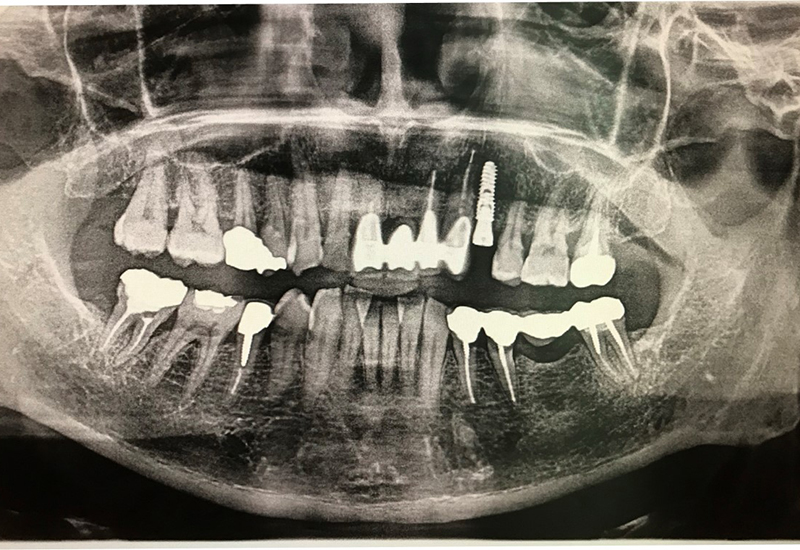

治療後 |

サージカルガイド

左上5にインプラント埋入の為のドリル用ホールあり